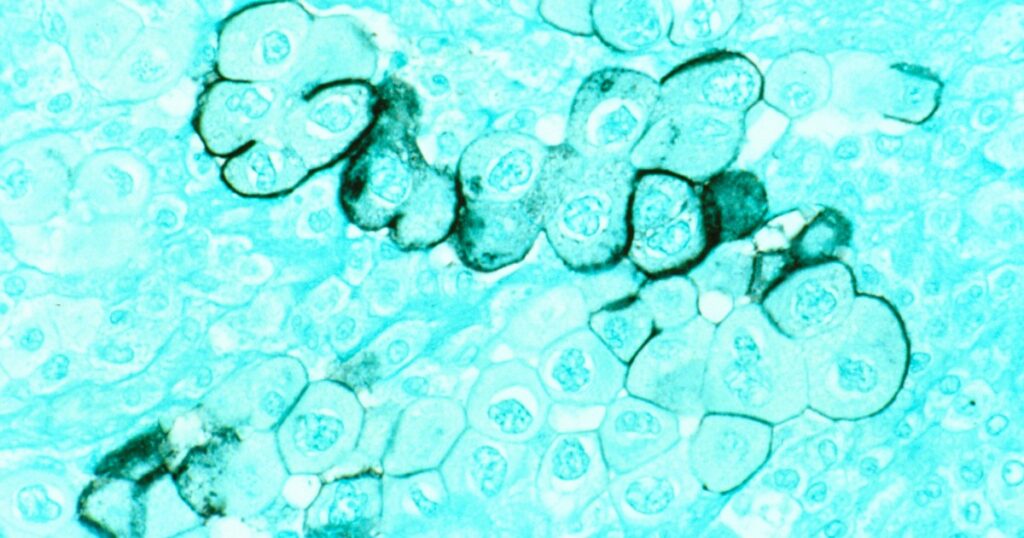

Pancreatic cancer has one of the lowest survival rates among cancer types, with less than 13% of patients surviving beyond five years after diagnosis. The disease is often diagnosed at an advanced stage, with nearly 90% of cases already progressing when detected.

Pancreatic cancer cells have a high tendency to spread rapidly to other parts of the body, usually after the primary tumor has grown large. Symptoms typically only appear in late stages, and there are currently no routine screening methods like mammograms or colonoscopies for this cancer.

A recent clinical trial evaluated the efficacy of an mRNA vaccine in pancreatic cancer patients who had undergone surgery to remove the tumor. Results showed that the vaccine elicited a response in half of the participants, generating tumor-targeting T cells that persisted for years. This promising outcome underscores the potential of mRNA vaccines in improving outcomes for pancreatic cancer patients.